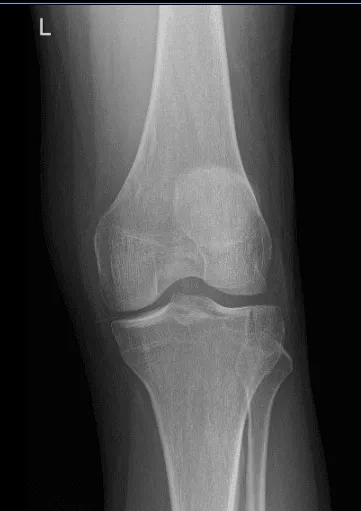

Post Operative Exam: General Appearance: swelling and tenderness and wound clean and dry, no warmth, appropriate range of motion, and neurovascular intact. New X-ray requested to see the improvement of patient condition.

There is a healing fracture of the lateral tibial plateau without depression of the articular surface. The joint spaces are preserved.